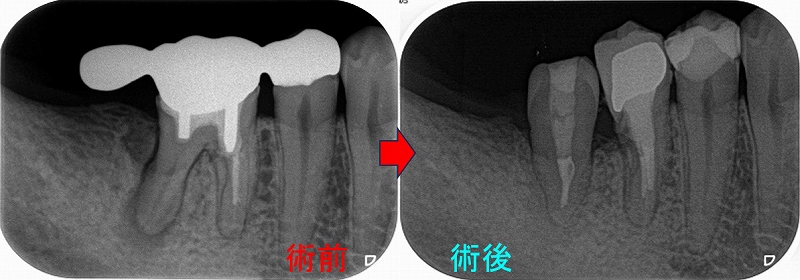

歯牙移植とヘミセクションから10年

先日昔治療させてもらった患者さんが詰め物が取れたということで来院されました。

この部位は

以前、延長ブリッジが入っていた歯

ふと、最近延長ブリッジ見なくなったなと思います。

(昔からあまりやらない方が良い治療だとは思っていましたが)

特に問題無かった歯なので、このままにしておいたのですが、

5年後

遠心根に透過像が出てきており、歯茎からは膿が出てきていました。

日本の根管治療の約6割には問題があるというはあながち間違いではないと思います。

とりあえず根管治療をして治すことにしましたが、

近心根にはパフォーレーション 手付かずの遠心根には破折線が見られ、

患者さんにどうします!?遠心根はまず残せない、近心根は残すことが出来るがパフォーレーションの位置的に長く持たない可能性がある。

不思議なんですが、遠心根は根管治療していないにも関わらず折れてきている。

イメージ的に根管治療を行い中を削って歯を弱体化させている近心根が折れるならまだ分かるのですが・・・

患者さんと話し合い、近心根はヘミセクションをして残す 遠心根は抜歯

右下7の所には親知らずの移植と計画をしました。

この後遠心根抜歯

口腔外科で移植をしてもらい、移植歯の根管治療を行い

ある程度咬めるように治させてもらいました。

今年になり患者さんが詰め物が外れたとのことで来院

10年経過して、そこまで悪い感じはありません。

患者さんにも「先生にそんなに持たないかもしれないよと言われていましたが10年持っています。意外と持つものですね!」と言われましたが、

ホント最初の延長ブリッジの方がかなり良い条件でしたが、折れてしまった。

パフォレーション+分割抜歯、移植した歯という条件の悪いケースで10年経過している。。。

たぶん、私がそんなに持たないかも!?と言った事でかばって咬むようにしているのが

今の状況を作っていると思いますが、ホント術者がどんなに頑張っても咬む力(歯ぎしり含め)で歯は必ず悪くなってきてしまいます。

こういうケースを見ると、患者さんの協力なしで歯を長く持たせることは難しいと感じます。

今回のケースは詰め物のやり替えだけ行えば、またしばらく使うことは可能でしょうd(^。^)